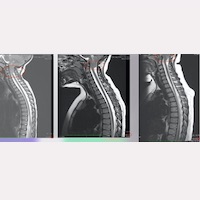

Si le corps, après l’intervention, présente certaines caractéristiques d’élasticité et de facteurs organiques qui lui permettent de retrouver la position anatomique la plus approprié ; il a été vérifié que dans certains cas les amygdales cérébelleuses ont tendance à remonter vers le foramen magnum.

Dans le cas de notre Institut, dans certains cas, cette augmentation est observée en 1-2 ans, tandis que dans d’autres cas, tout au long des 5-10 premières années postopératoires (Fig. 1).

Le fait qu’au moyen d’une action chirurgicale indirecte et située dans une autre zone anatomique, le changement de la position des amygdales cérébelleuses soit produite, ainsi que l’amélioration clinique ressentie par les patients ; Pour nos médecins, c’est une confirmation supplémentaire que la cause de la pathologie a été éliminée, cessant d’être active et de tirer la moelle épinière, le tronc cérébral et la colonne vertébrale.